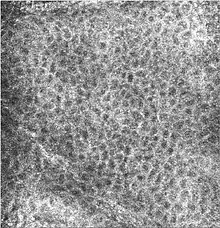

![]() Microscopic image of the epidermis, which constitutes the outer layer of skin, shown here by the white bar | |